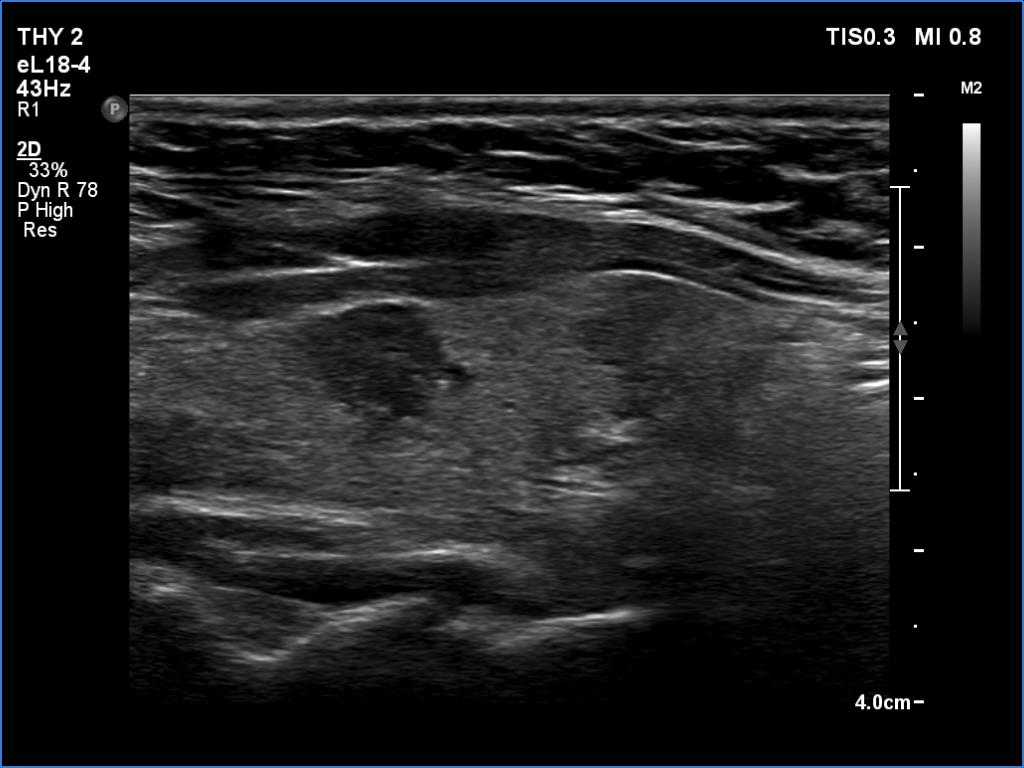

First examination (first and second rows of images):

Ultrasonography. The thyroid was echonormal or minimally hypoechoic and had several discrete, more hypoechoic areas. Two of them in the left lobe were remarkable because of irregular borders and nonparallel orientation.

Cytology was performed from the larger lesion in the left lobe and resulted in Hashimoto's thyroiditis.